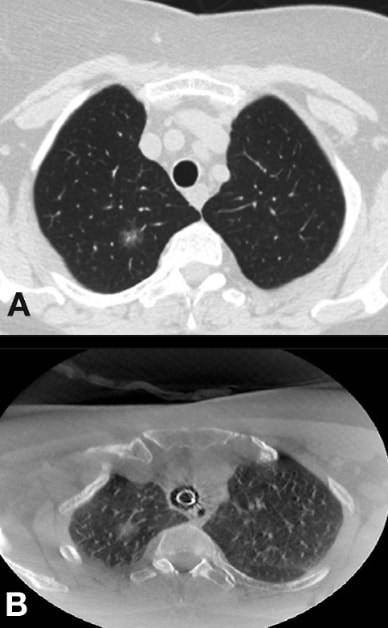

Comparison of standard CT and cone-beam CT (CBCT) in the same patient. Note the same nodule looks to be in a different position. A. Pre-op standard breath-hold CT. B. Intra-op cone-beam CT.